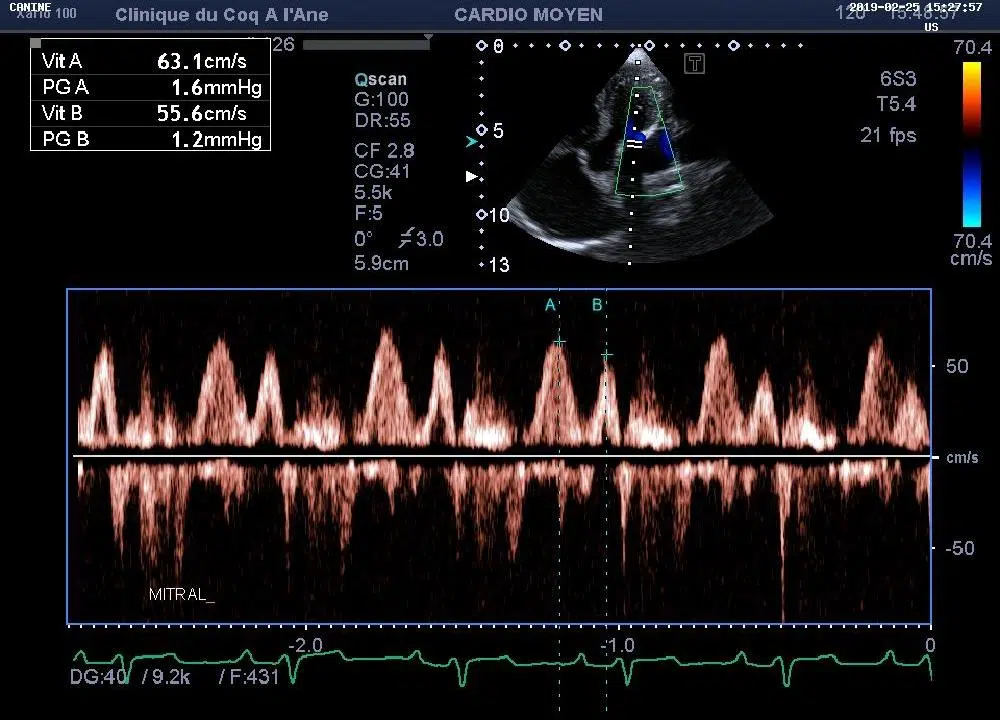

• 2 échographes dédiés aux petits animaux munis respectivement de 2 et 4 sondes